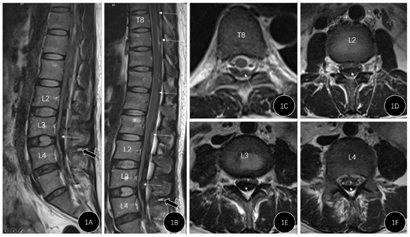

患者于LP后第7天出现下肢肌力减退、二便障碍时行腰椎磁共振平扫检查,见图1。磁共振显示胸腰段扫描范围内椎管内血肿,腰段蛛网膜下腔间隙消失,脊髓圆锥及马尾神经受压。根据磁共振的影像,T1及T2相均表现为低信号为主的混杂信号,考虑血肿。根据轴位影像的血肿形态,血肿更偏向梭形,尤其胸8节段可见蛛网膜下腔并未受累,故考虑为硬膜外血肿。

诊断:椎管内血肿,硬膜外血肿可能性大。

根据患者抗凝治疗的基础状态,LP病史,LP后开始出现腰痛、逐渐加重并出现下肢无力、二便障碍的症状,腰椎磁共振检查示椎管内低信号为主的异常混杂信号,考虑椎管内血肿诊断明确。根据血肿梭形形态,胸8节段可见蛛网膜下腔并未受累,故考虑为硬膜外血肿可能性大。

鉴别诊断:(1)蛛网膜下腔血肿。椎管内血肿第二常见位置,可因穿刺损伤根动脉或根静脉导致出血[1],少量出血则被脑脊液稀释,大量出血可形成血肿,血肿位于硬膜下、蛛网膜下腔,血肿围绕脊髓和马尾神经根,该患者血肿局限于椎管后方,将脊髓和马尾神经向前方推挤,且胸8节段可见蛛网膜下腔并未受累,故考虑硬膜下血肿可能性小。(2)硬膜下蛛网膜外血肿。该腔隙为潜在腔隙,且其内无血管结构,文献中尚无确凿证实该位置血肿的报道,故术前未考虑该位置的血肿。